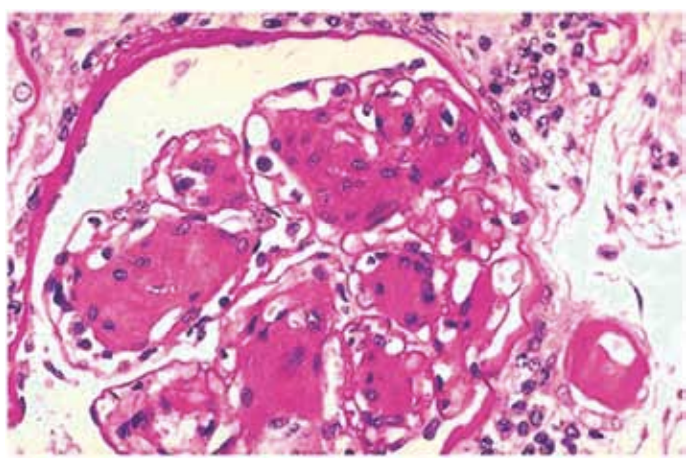

Homem, 54 anos, diagnóstico de diabetes mellitus há

4 anos, desconhecia o valor de sua glicemia antes do

diagnóstico. Na consulta inicial, negou antecedentes patológicos. Exame físico: PA 135 x 80 mmHg e edema de

membros inferiores ++/4. Exame de fundo de olho normal. Exames recentes: creatinina sérica = 1,3 mg/dL;

exame de urina: proteína +++/4, hemácias = 80.000/mL

(VR até 10.000), leucócitos = 8.000/mL (VR até 10.000);

proteinúria 3,8 g/24horas; albumina sérica 3,1 g/dL. Realizada biópsia renal, na qual foi identificada a seguinte

lesão glomerular na microscopia óptica:

(Arquivo pessoal; imagem usada com autorização)